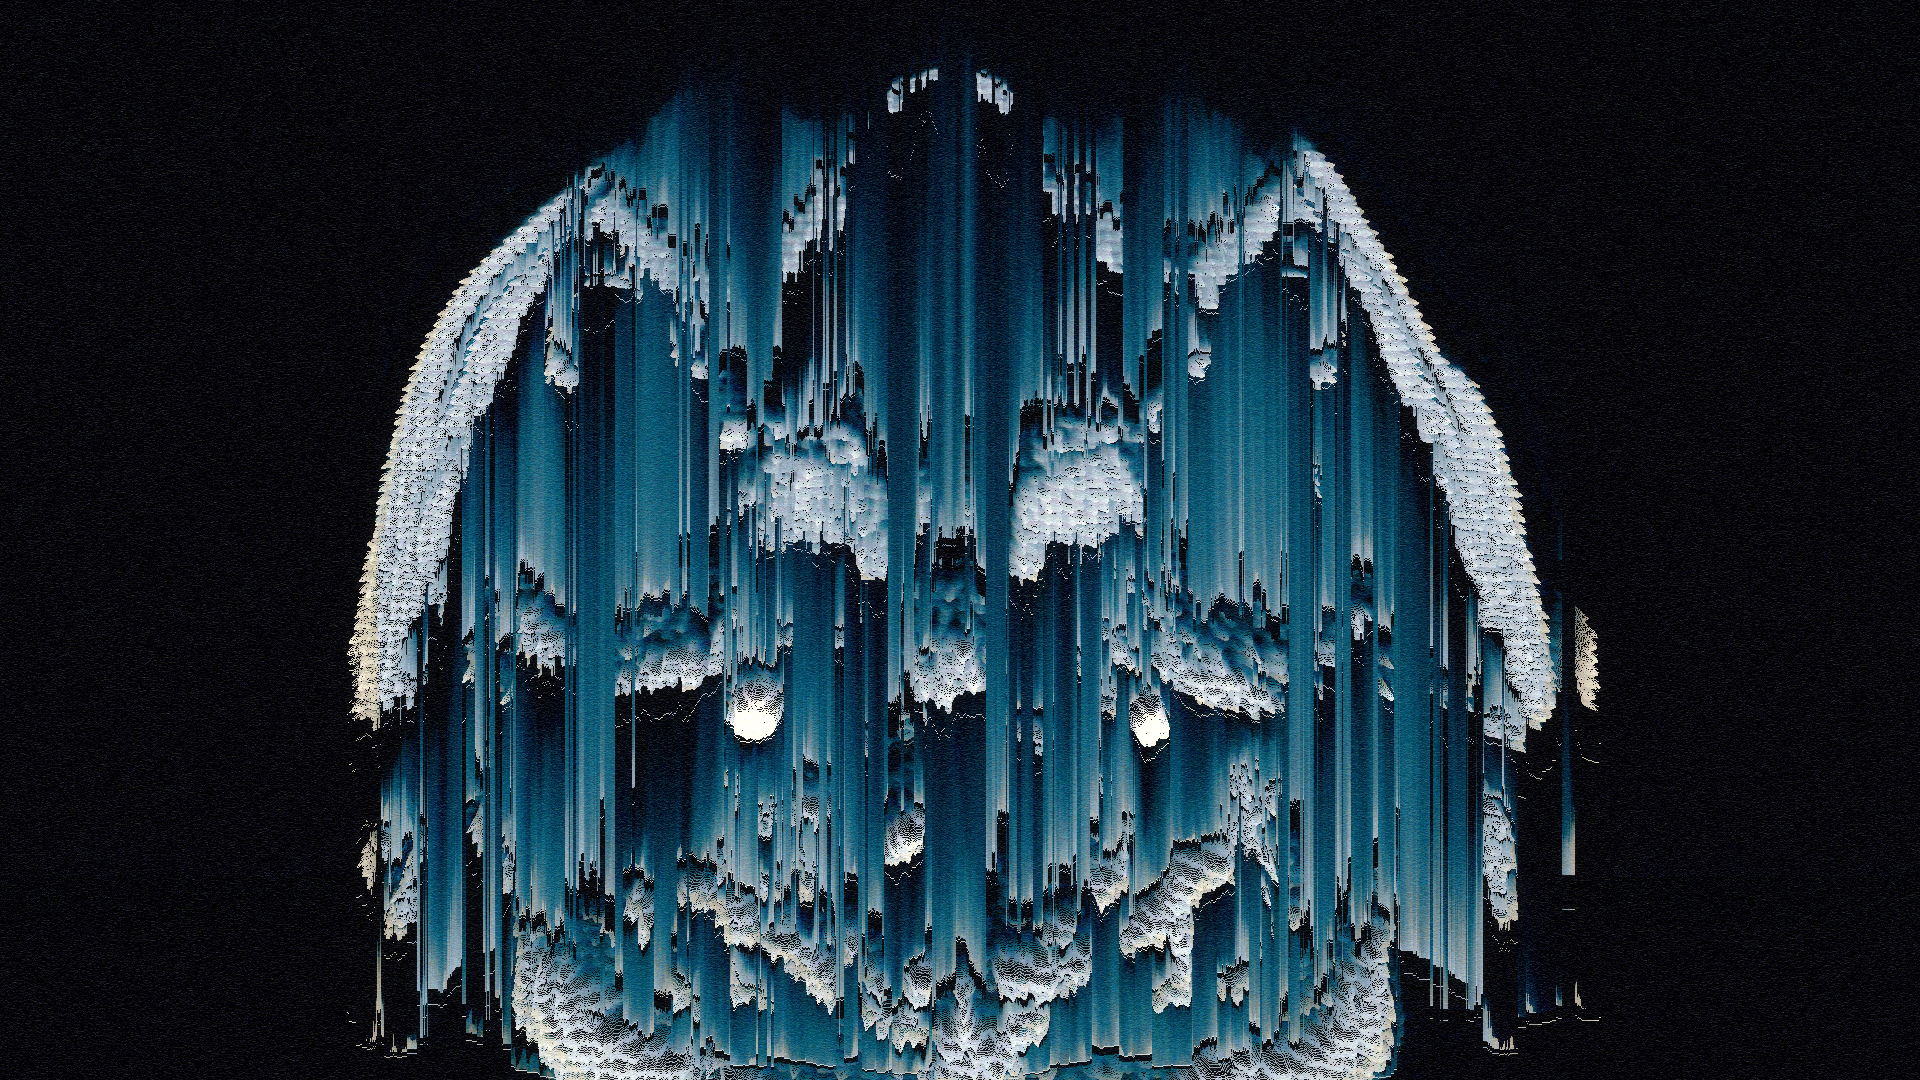

I recently developed style frames and animations for a television commercial. The main topic of the ad was to reflect Alzheimer's disease and what happened in the patient's brain.